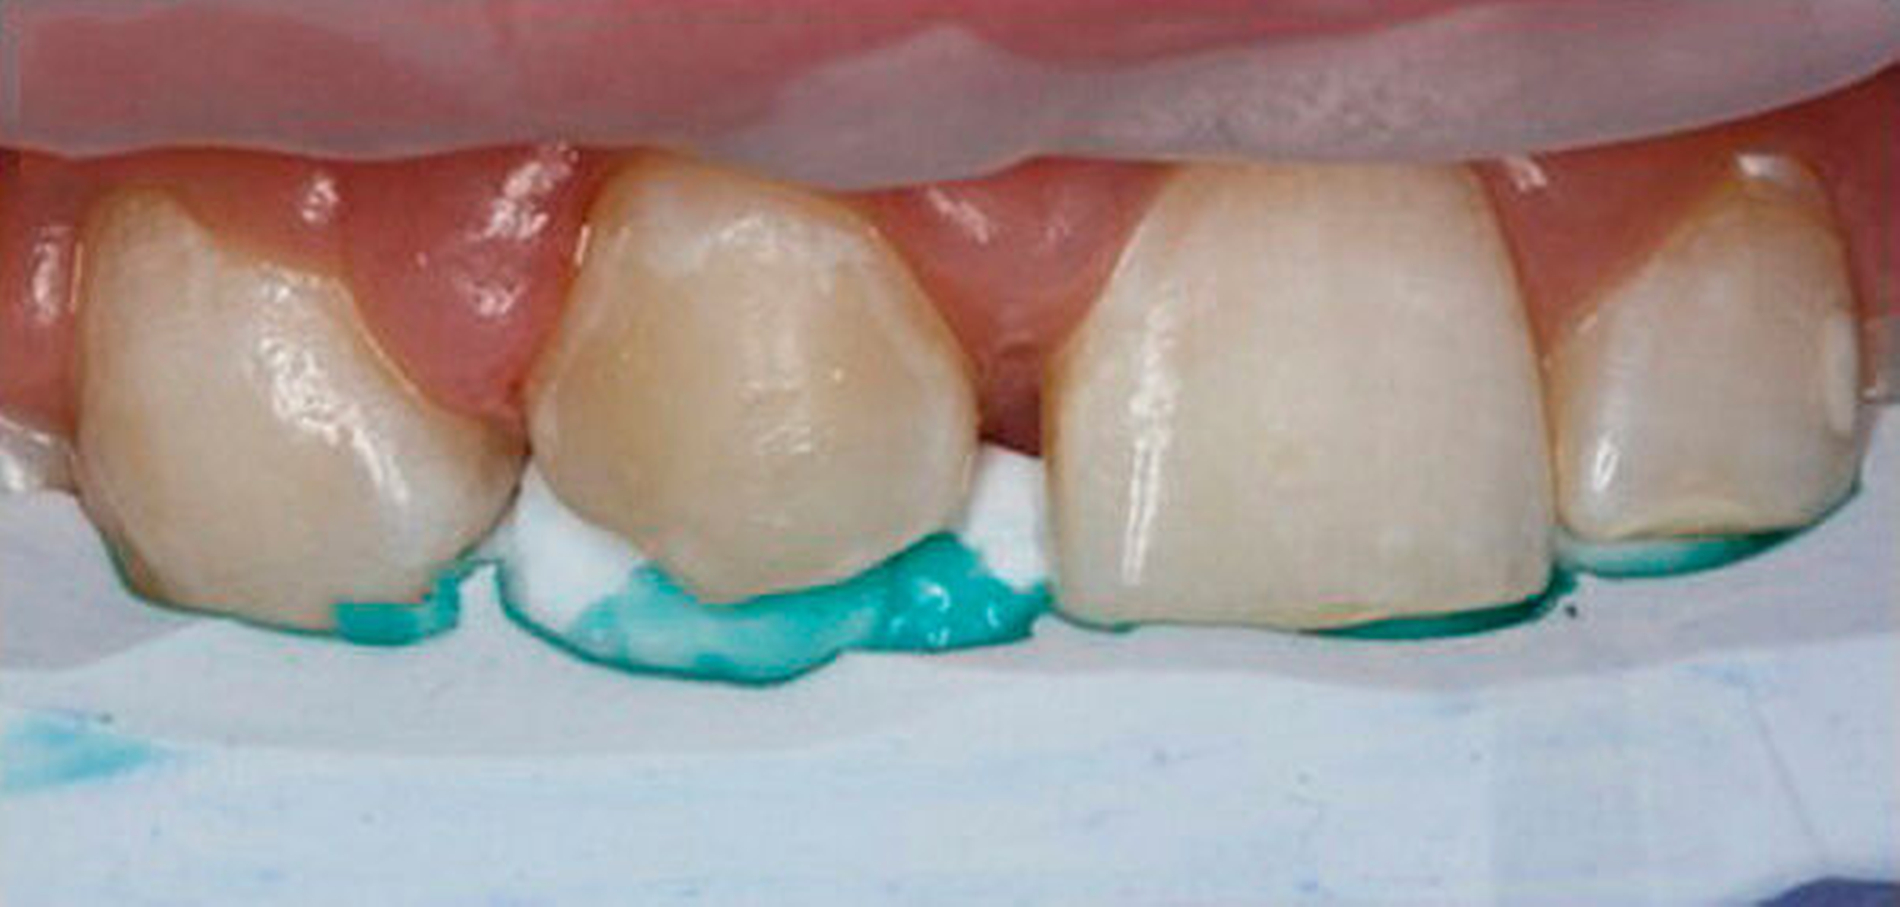

Die Rekonstruktion von Zähnen mit Komposit ermöglicht eine direkte und maximal zahnerhaltende Therapie, bei der die Zahnhartsubstanz nicht oder nur minimal im Sinne einer Anschrägung abgetragen werden muss. Im Vergleich zur Rekonstruktion mit keramischen Veneers muss dabei in der Regel wesentlich mehr Zahnhartsubstanz geopfert werden, um die nötigen Keramikschichtstärken einhalten zu können. Reparaturen, Farb- und Formanpassungen lassen sich mit der Komposittechnik im Vergleich zu Keramikrestaurationen immer wieder anpassen. Insbesondere bei jungen Patienten im Wachstum ist dies von Vorteil, um bei Veränderungen der Gingivaverhältnisse die rekonstruierten Zähne ihren Nachbarzähnen anzupassen (Verschluss schwarzer Dreiecke, zervikale Ausformungen).